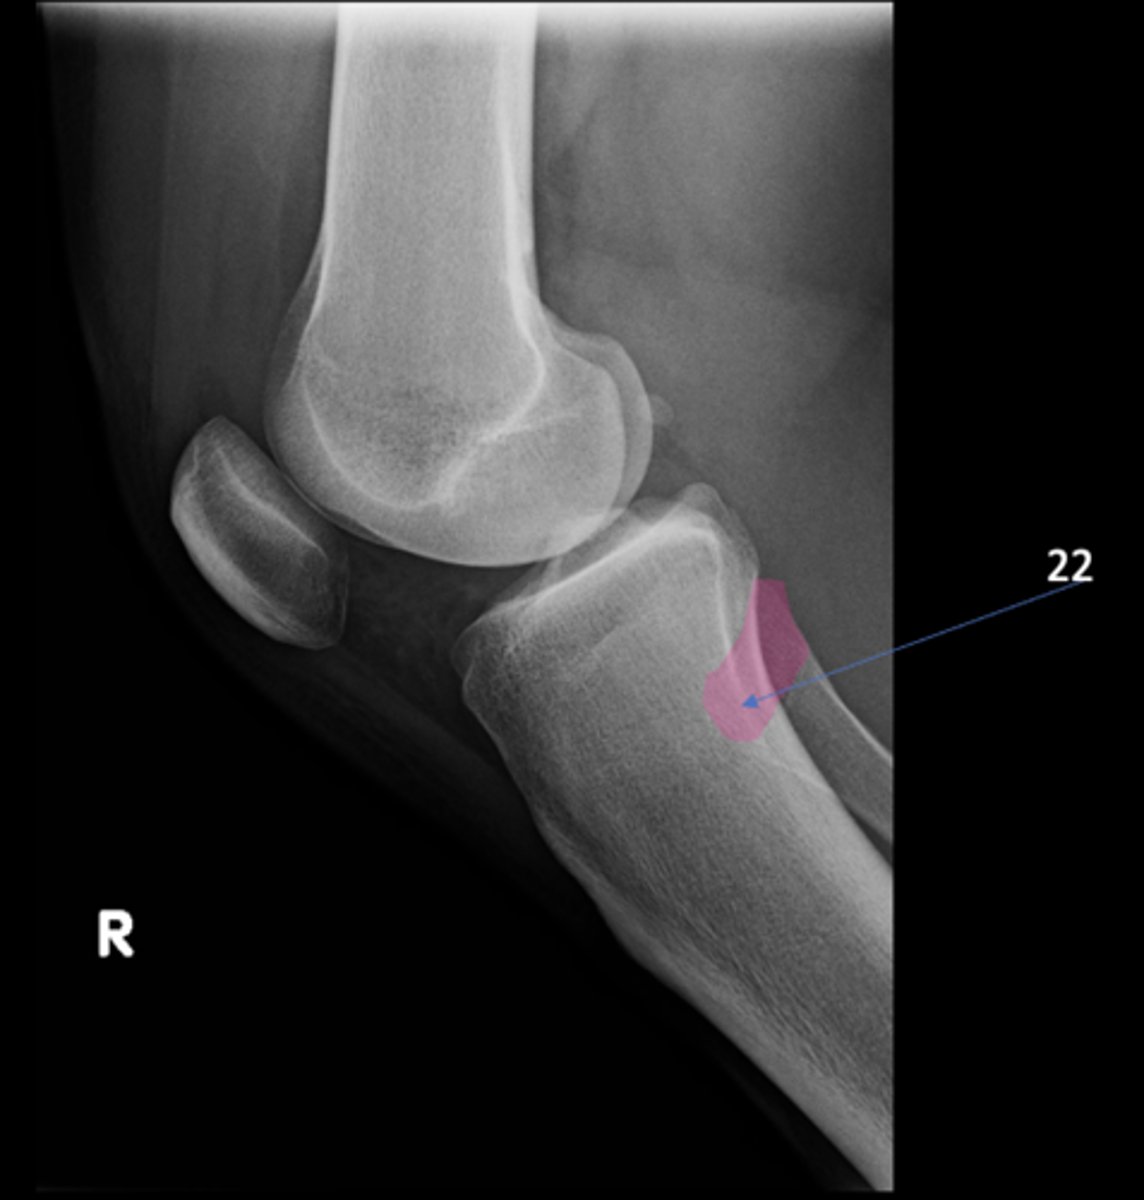

ID 9

<p>ID 9</p>

10

New cards

Left obturator foramen

ID 10

<p>ID 10</p>

11

Right posterior superior iliac spine

ID 11

<p>ID 11</p>